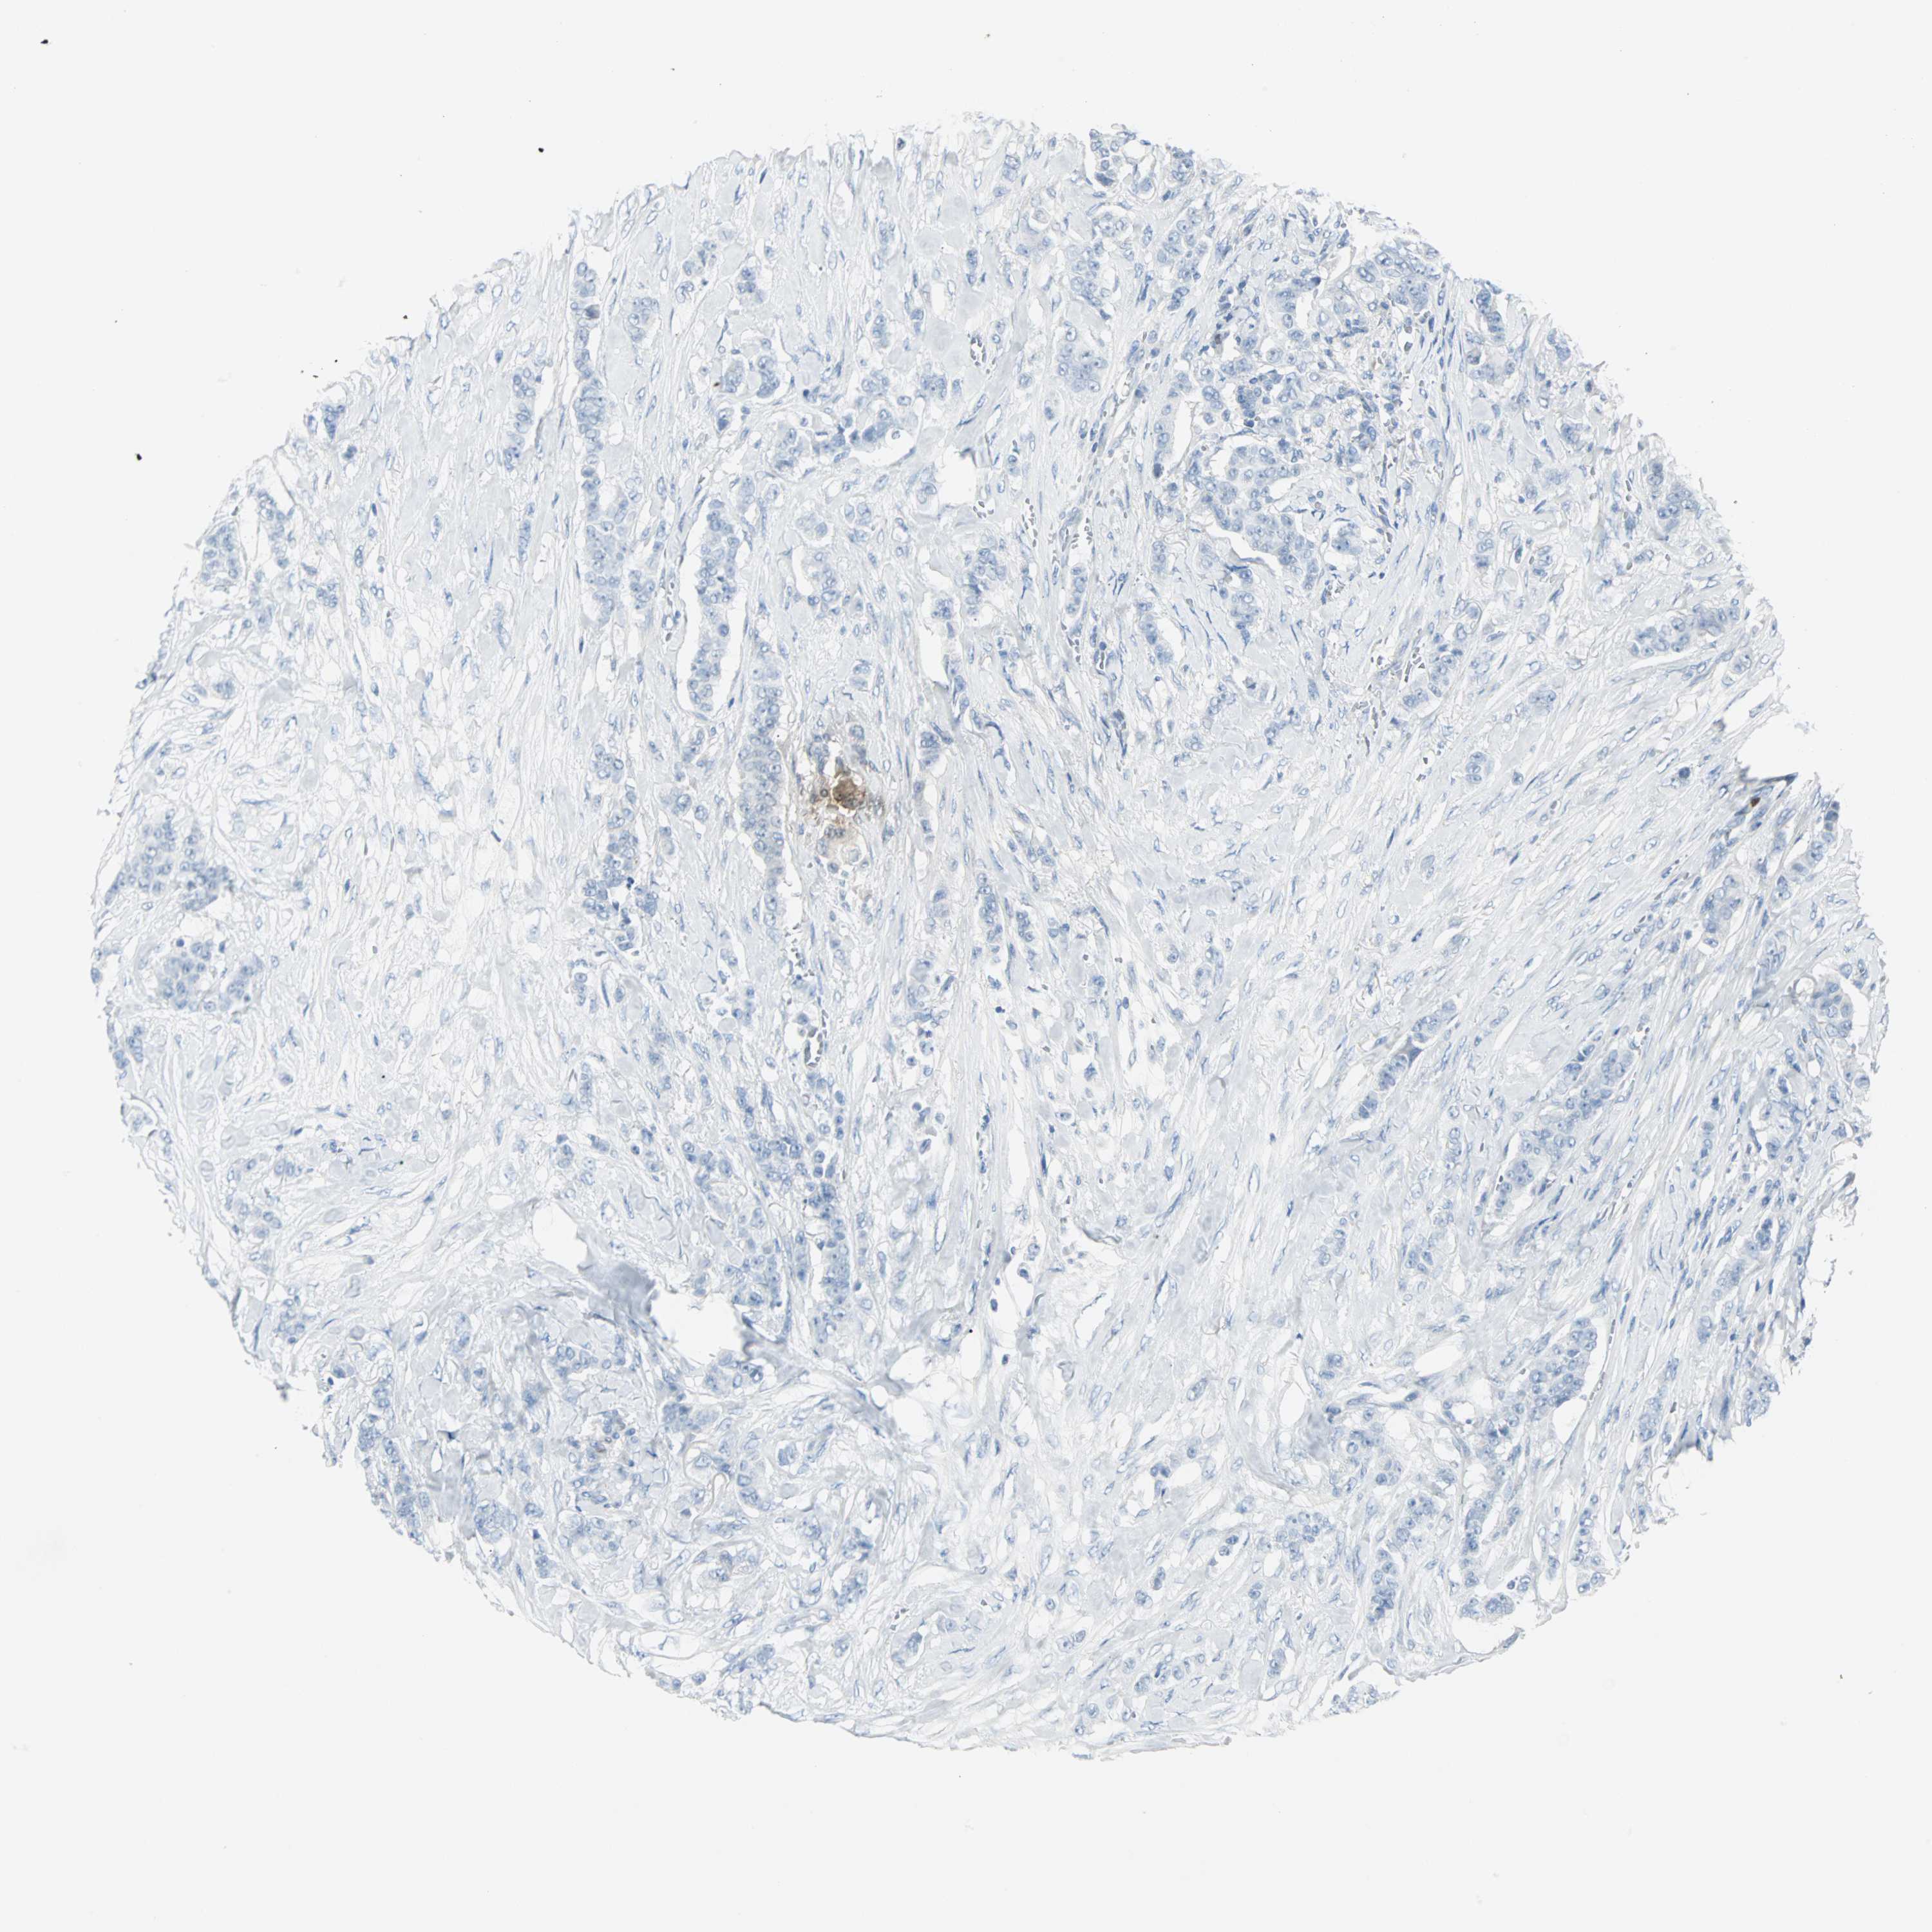

CANCER BREAST CANCER Show tissue menu

BRCA TCGA BRCA VALIDATION PROTEIN EXPRESSION